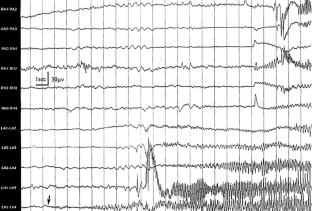

Magnetic resonance imaging combined with electroencephalography (EEG), electrocorticography, and depth-electrode EEG was valuable to localize complicated epileptogenic zones of the patients with DNT. Neuropathological examinations of the peritumoral cerebral cortex presenting abnormal spikes showed different histopathological grades of neuronal migration disorder (NMD). The tumor cells in DNT disclosed increased immunopositivities of N-methyl-d-aspartate receptor 1 (NR1) and NR2A/B, and peritumoral epileptogenic NMD revealed increased immunopositivities of GluR2 and GluR3. The amplification of ionotropic glutamate receptor subunits in the tumor and peritumoral NMD may be the underlying cause of epileptic seizures in DNT patients.

Fig. 1